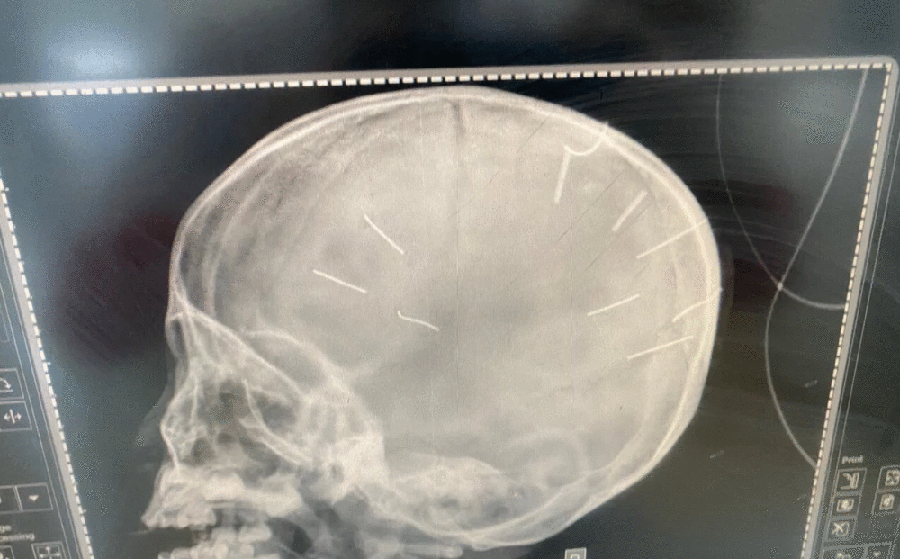

Công an điều tra nhân tình người mẹ vụ bé gái 3 tuổi bị vật nhọn ghim vào đầu

20/01/2022 09:56

Công an triệu tập mẹ bé gái 3 tuổi có vật giống đinh ghim trong hộp sọ